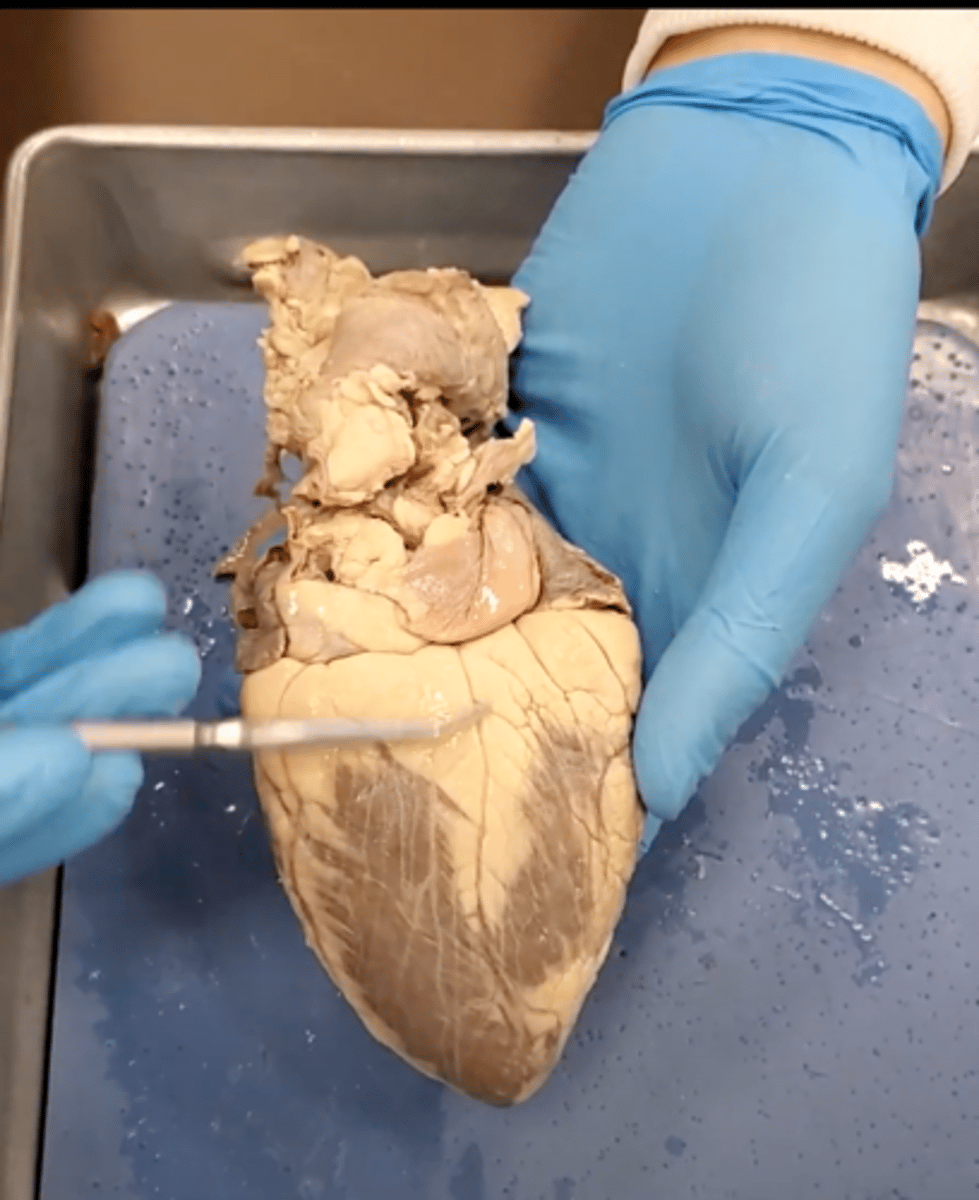

Tricuspid Valve (Right Atrioventricular Valve)

1-valve

Bicuspid valve (Left Atrioventricular Valve)

2-valve

Pulmonary Semilunar Valve

3-valve

Aortic Semilunar Valve

4-valve

Right Atrium

1-chamber

Left Atrium

2-chamber

Right Ventricle

3-chamber

Left Ventricle

4-chamber

Inferior Vena Cava

5-A vein that is the largest vein in the human body and returns blood to the right atrium of the heart from bodily parts below the diaphragm.

Superior Vena Cava

6-A vein that is the second largest vein in the human body and returns blood to the right atrium of the heart from the upper half of the body.

Aorta

7-The large arterial trunk that carries blood from the heart to be distributed by branch arteries through the body.

Pulmonary Trunk

8-carries blood from right ventricle to pulmonary arteries

Pulmonary veins

9-a vein carrying oxygenated blood from the lungs to the left atrium of the heart.

pulmonary trunk (model)

yellow sash of fat that tells you this if the front side of the heart (model)

t-shaped ribbon of fat on back side of heart (model)

Left ventricle (model)

has the most muscle mass because it has to pump blood to the whole body

apex (model)

base (model)

where everything connects

yellow sash of fat that tells you this if the front side of the heart (dissection)

pulmonary trunk (dissection)

t-shaped ribbon of fat on back side of heart (dissection)

left auricle (dissection)

right auricle (dissection)

left ventricle (dissection)

right ventricle (dissection)

right atrium (dissection)

left atrium (dissection)

bicuspid valve (dissection)

tricuspid valve (dissection)

aortic semilunar valve (dissection)

located between the left ventricle and the aorta

chordae tendineae (dissection)

thin bands of fibrous tissue that attach to the valves in the heart and prevent them from inverting